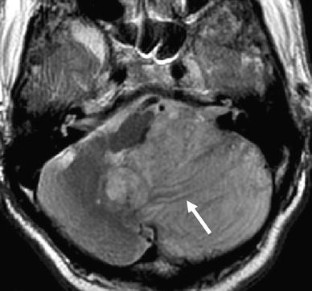

A case of Lhermitte-Duclos disease presenting high FDG uptake on FDG-PET/CT

Lhermitte-Duclos Disease (LDD) is a rare cerebellar lesion that has long been controversial as to whether the entity is a hamartoma, a malformation, or a neoplasm. Recent advances in metabolic imaging and molecular biology have unveiled biological features of LDD and a close relationship between LDD and Cowden disease. Adult onset LDD is now considered identical to Cowden disease in a US guideline. We present a case of LDD, in which high fluorodeoxy glucose (FDG) uptake was shown on PET/CT. We performed dual time point scans, in which a delayed scan exhibited more intense FDG uptake by the hamartomatous lesion than an early scan. We must remain aware of the possibility of LDD when intense accumulation is observed in a cerebellar lesion on FDG-PET/CT imaging.

Fig. 1

Fig. 2

Fig. 3